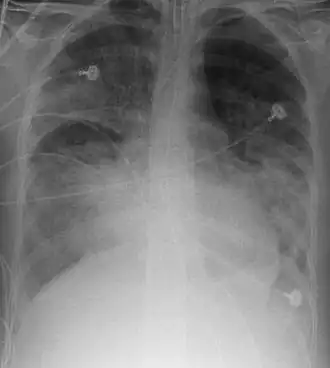

Description de cette image, également commentée ci-après

Le SDRA est défini par l'association de quatre critères : détresse respiratoire depuis moins d'une semaine, opacités pulmonaires bilatérales sur la radiographie thoracique ou la tomodensitométrie (TDM), pas d'argument pour une cause cardiaque d'œdème pulmonaire, et hypoxémie.

• opacités pulmonaires bilatérales floconneuses sur la radiographie thoracique ou la TDM, non expliquées par un épanchement, une atélectasie, ou des nodules ;